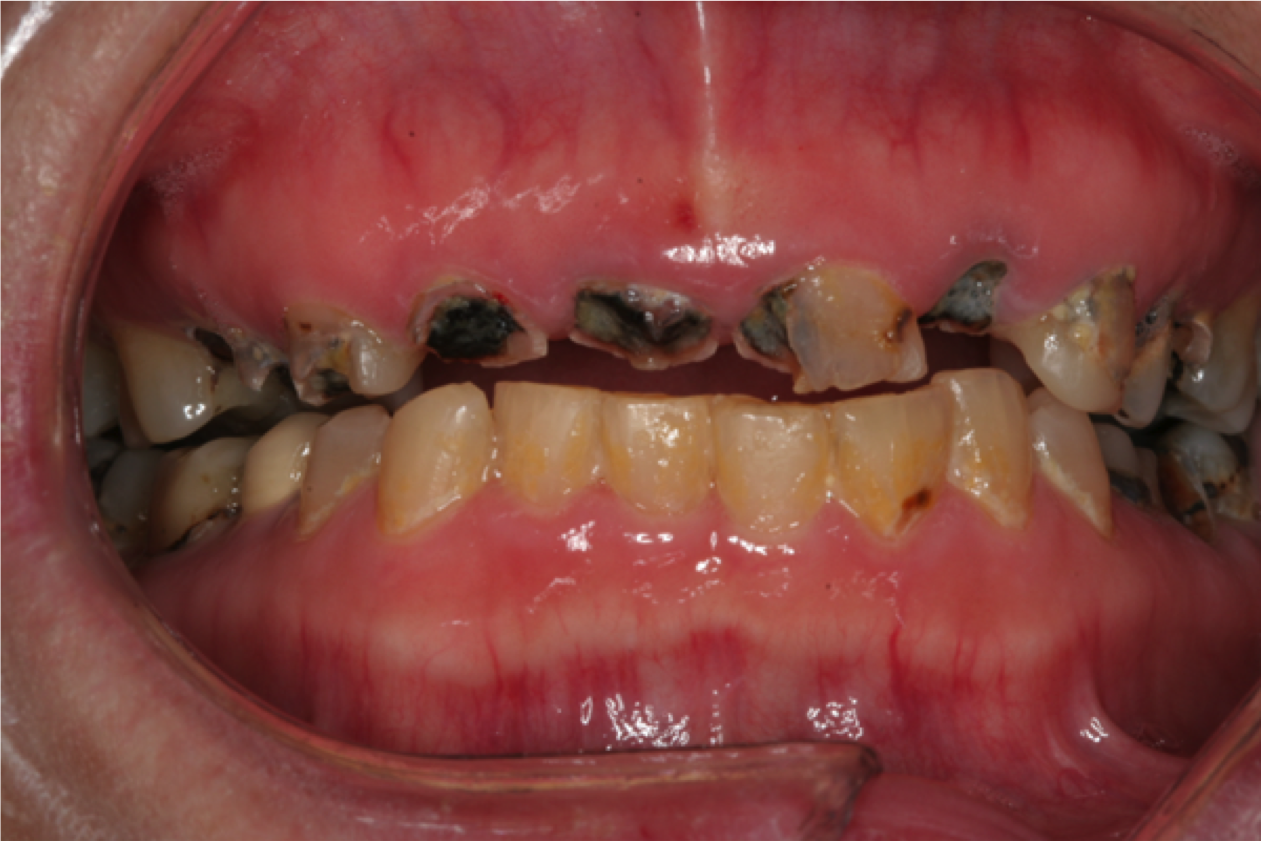

Rapidly advancing and rampant caries can result in pain, acute and chronic infections, and tooth loss leading to resultant functional, esthetic, and psychological sequelae of poor oral health.25 Left untreated, root caries can result in the loss of the crown and a retained root that can be a chronic source of inflammation (Figure 2). This, in turn, causes exposure of the pulp chamber, creating a risk for chronic and acute apical periodontitis.20

Fig 2. Rampant caries and nonrestorable root tips.